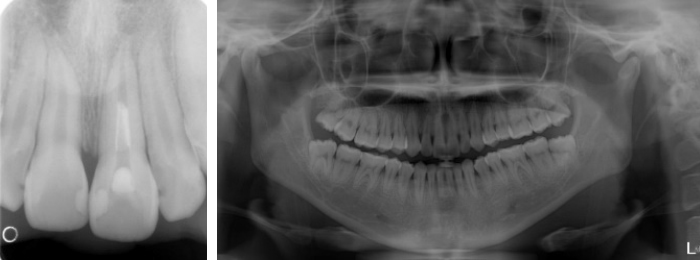

デンタル、パノラマ撮影

デンタル撮影は口の中にIPといわれるフィルムのようなものを入れ、それぞれの歯について撮影します。 パノラマ撮影とは広い範囲を1枚におさめた写真で、歯全体・顎・顎関節等の撮影をします。パノラマ撮影では下図のように1度に全体像を撮影することができます。